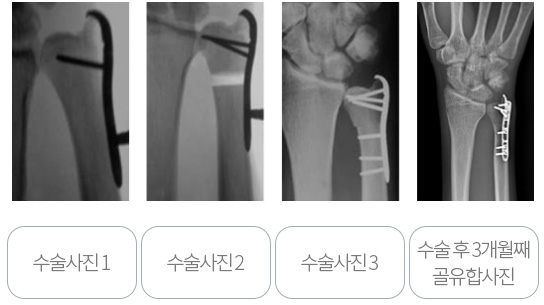

수술시 관절내시경을 통하여 연골상태를 확인하고 삼각섬유연골 파열이 있을 시 봉합술을 같이 시행한 뒤, 척골의 길이를 단축하는 척골단축술을 시행합니다. 단축할 길이가 2mm이하라면 관절내시경(Wafer 술식) 만으로 치료가 가능하나, 2mm이상이라면 관절내시경 만으로는 결과가 좋지 않으며, 통증이 남고 재발하는 경우가 흔합니다.

이때에는 금속판을 이용한 척골 단축술을 시행하여 많은 환자에서 좋은 결과를 보이고 있습니다. 아래 사진은 고식적 방법의 척골 단축술이며 국내 또는 국외에서 많이 시행되고 있는 방법입니다. 4mm 이상의 뼈를 단축할 수 있고, 장점이 많으며 좋은 결과를 보고하고 있으나, 절개부위가 크며 절골술 부위의 불유합이 발생할 수 있다는 단점이 있습니다.

본원에서는 원위 골간단부 척골단축술과 관절내시경 치료를 주로 시행합니다. 절개부위를 최소화 하고 불유합 가능성을 낮추며, 한번의 절개로 삼각섬유연골 봉합까지 같이 시행할 수 있다는 장점이 있습니다.